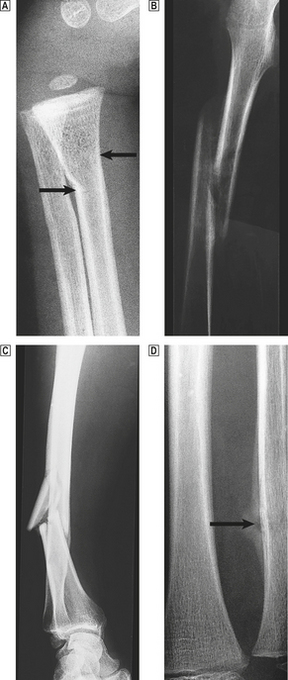

Fractures in normal bone are the result of substantial trauma, such as direct violence or a sudden unexpected fall. The precise site of fracture, the nature and direction of the fracture line, and the speed of the subsequent repair process depend very much on the age of the patient, the particular bone involved and the precise pattern of injury (Fig. 25.3).

image

Fig. 25.3 Fracture types and fracture healing. image A greenstick fracture of the distal radius in a young child (arrowed). image A displaced spiral fracture of the femur in a child. image A comminuted fracture of the tibia. One fragment of bone has almost separated from the shaft. image A healing fracture of the ulna. The site of the break is just visible and is surrounded by callus (arrowed).